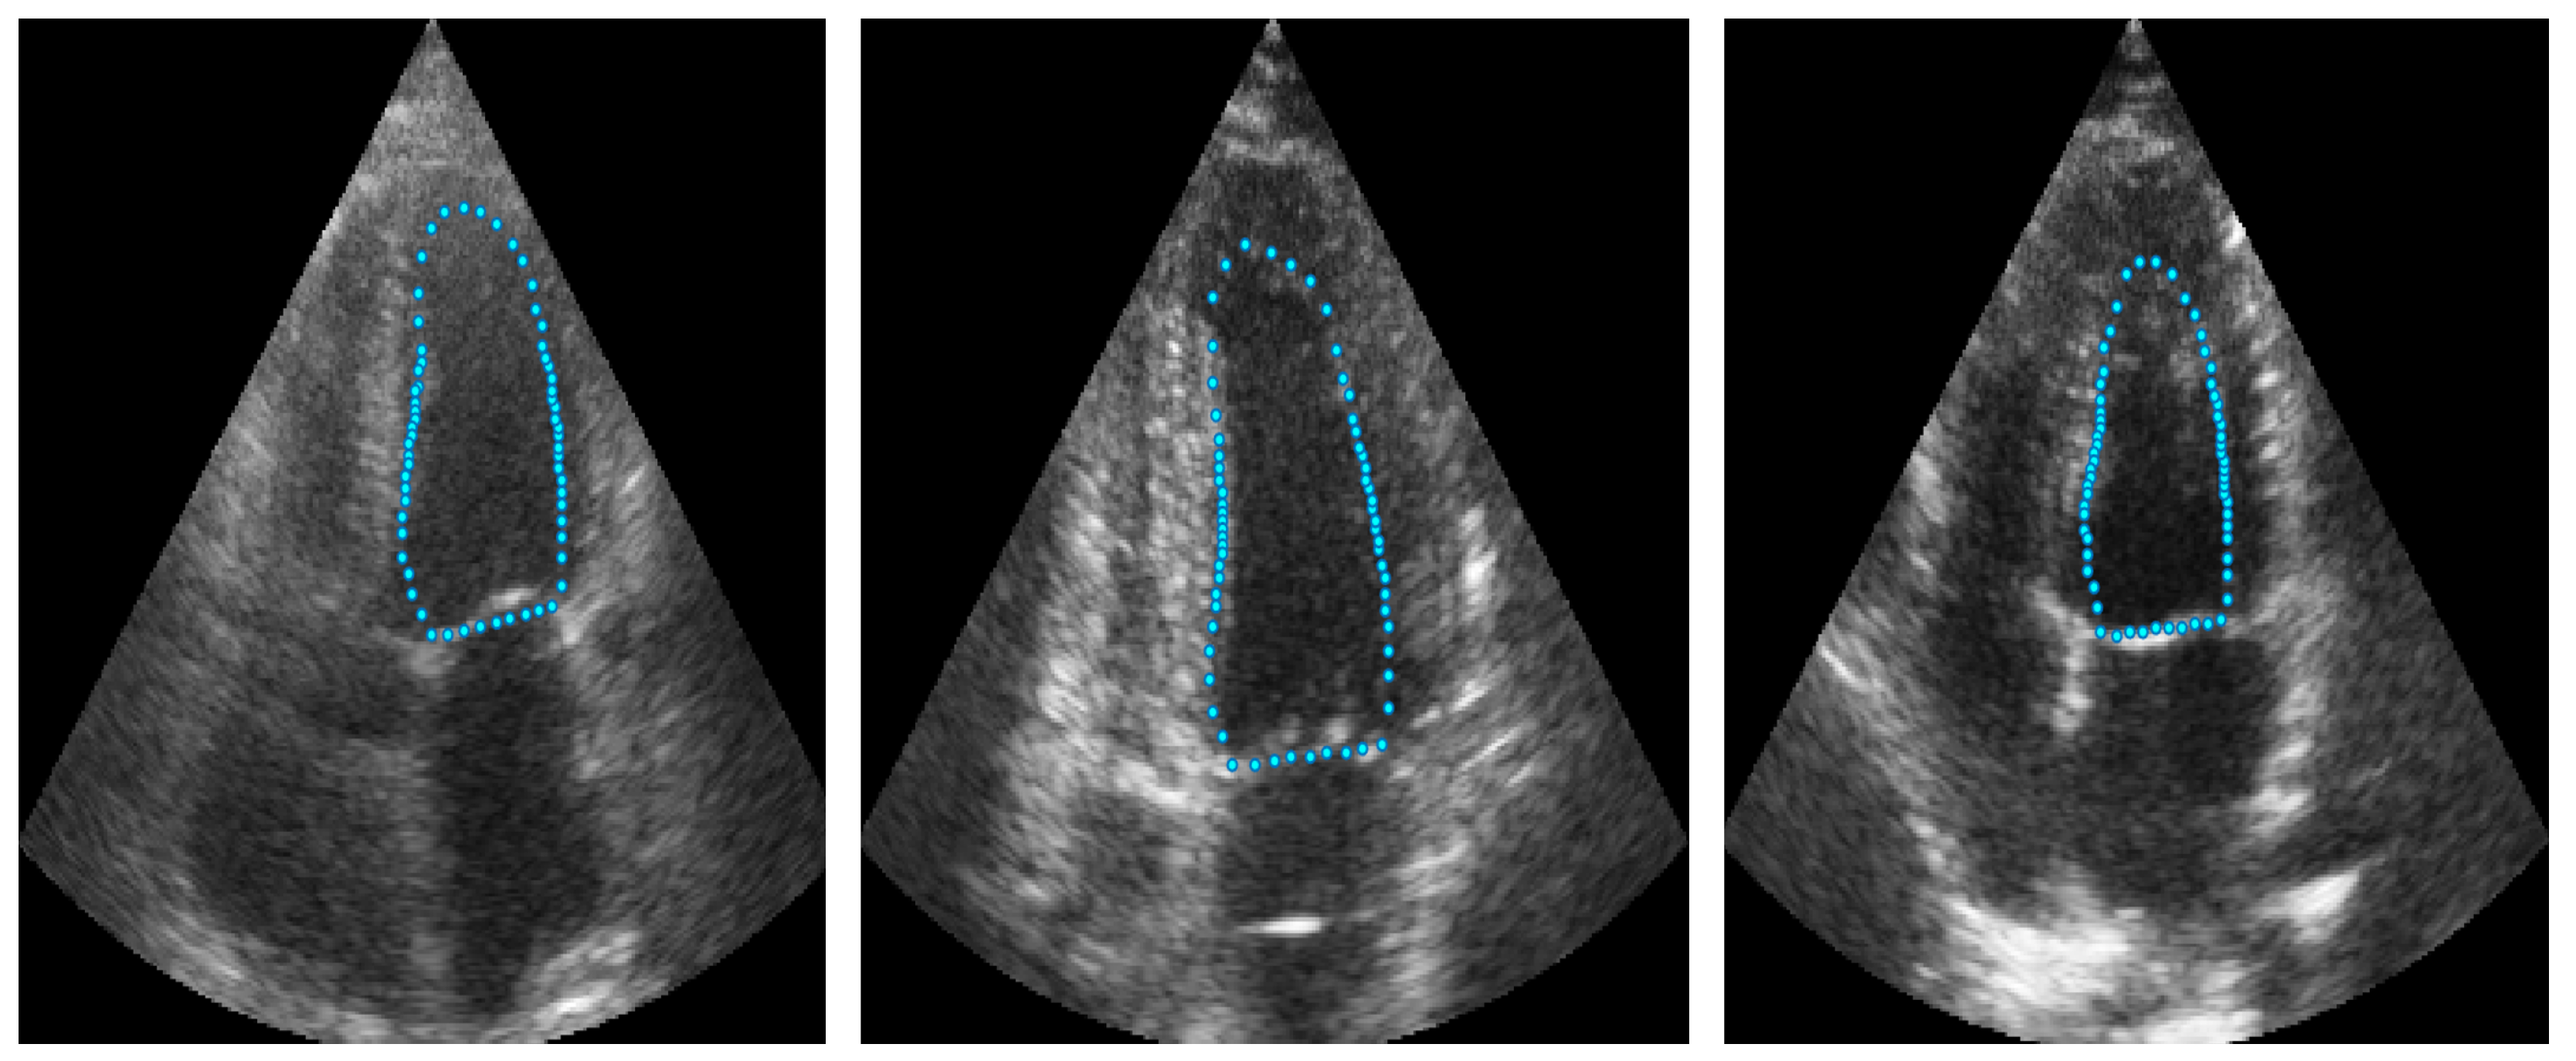

3.1. Point Distribution Model of the Left Ventricle (LV-PDM)

Point distribution models (PDMs) provide a compact representation of a class of shapes; in this case, the shape of the left ventricle. Construction of the PDM was performed as described in [30] by annotating landmark points around the contour of each left ventricle previously marked by an expert. For this LV-PDM, 64 landmarks were selected, which accurately represent the contour of the left ventricle, as shown in Figure 2, using the training data described in Section 4.1. Principal component analysis (PCA) of the normalized landmark training set resulted in five principal modes of variation in the shape of the LV, contained in a principal eigenvector matrix (), which allows creating new instances of the LV shape using Equation (1). Figure 3 shows some examples of shapes, corresponding to different values of the five weights in vector b.

Figure 2.

Example of landmarks sampled in LV ultrasound images.